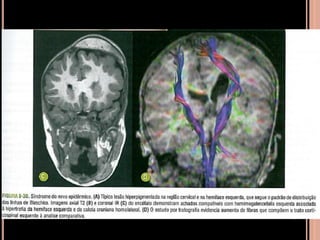

SÍNDROME DO NEVO EPIDÉRMICO

 Nevo sebáceo de Jadassohn, retardo mental e

crises epilépticas;

 Placas delimitadas, elevadas, hipercrômicas de

aspecto aveludado;

 Hemimegalencefalia homolateral ao nevo

epidérmico;

 hemihipertrofia facial pode ocorrer;